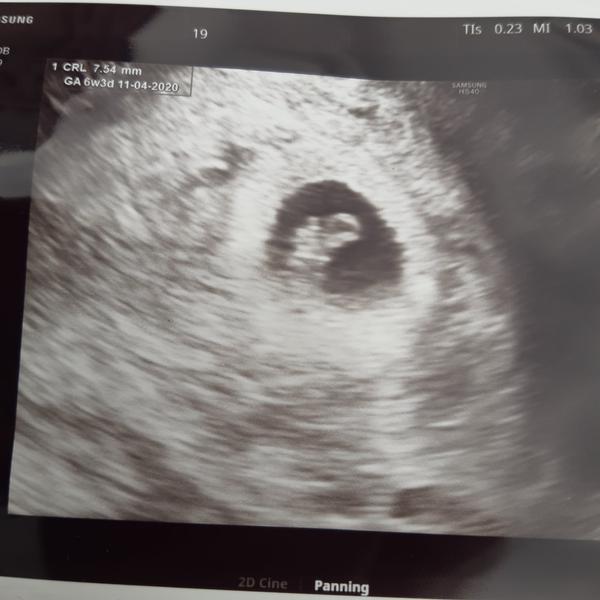

@balogis já jdu na kontrolu zítra, to budu 6+5 tak uvidíme... Srdíčko se určitě ukáže, máš ještě čas, třeba na lepším přístroji už by bylo viditelné, těžko říct. I když chápu tvůj stres, věřím, že to bude dobrý! Držím palce 😊

Pro všechny 😊 - holky držte se ať je vám zle, nebo vás trápí něco jiného, vše dopadne tak jak má 😊 já jsem dnes 6+4 cítím žaludek a občas takovou slabost, ne na omdlení, ale vyloženě že se mi chvěje celé tělo a nemám sílu. Zatím mi bylo nejhůře asi před pár dny v noci, kdy jsem fakt myslela, že už poběžím, ale na štěstí jsem to ustála 😊 zítra jdu na první kontrolu, tak uvidíme, co uvidíme 😁 snad si přinesu taky foto a bude vše v pořádku 😊

@balogis Já byla u dr na první kontrole 7+0, srdíčko už bylo... takže u tebe je určitě ještě moc brzy, bude to dobré, držím pěsti!